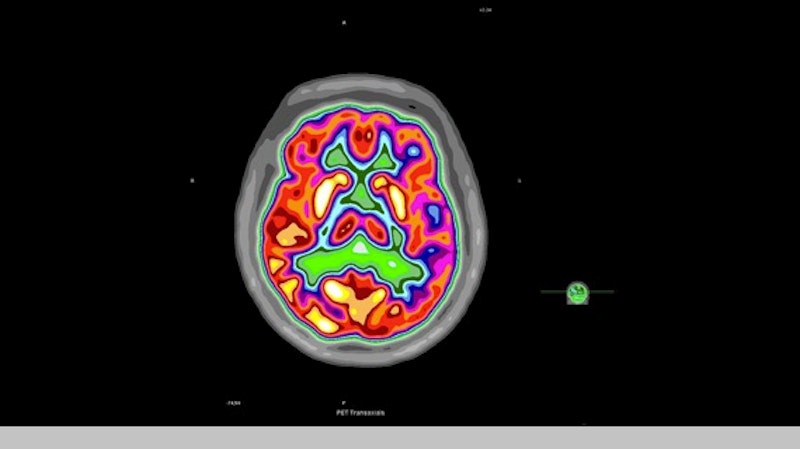

Positron emission tomography PET uses very small amounts of radioactive glucose to produce 3D and cross-sectional images of the body. This price represents the PET scan of the brain chest or the whole body whether with or without simultaneously using the CT scan. PSMA is a type of protein found on the surface of prostate cancer cells in high.

Above prices quoted are all-inclusive prices for a Cervical Spine PET Scan which includes imaging center fee radiologist fee and a copy of your scan images and report. PET Scan Near Me. A PET scan shows how the tissues and organs inside your body are working.